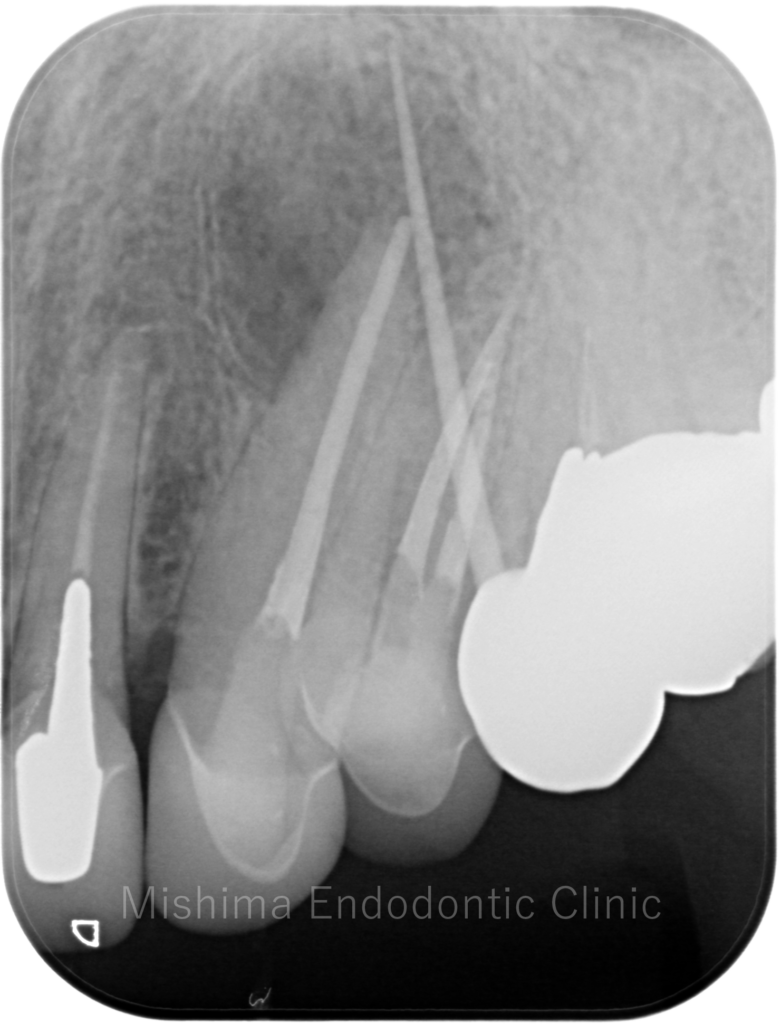

Before

| 主訴 | 他院にて歯根端切除術を受けたが、腫れてきた |

| 治療内容 | 他院にて歯根端切除術の既往があり、その後サイナストラクトを発現。再歯根端切除術にて対応。 |

術前